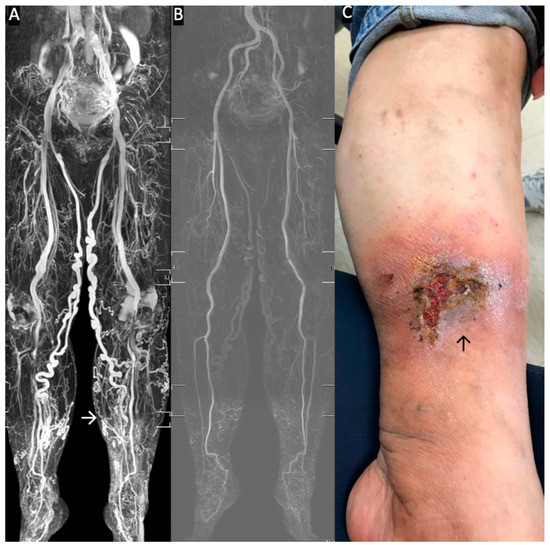

Stasis Leg Ulcers: Venous System Revises by Triggered Angiography Non-Contrast-Enhanced Sequence Magnetic Resonance Imaging

- Chen, C.W.; Tseng, Y.H.; Lin, C.C.; Kao, C.C.; Wong, M.Y.; Lin, B.S.; Huang, Y.K. Novel Diagnostic Options without Contrast Media or Radiation: Triggered Angiography Non-Contrast-Enhanced Sequence Magnetic Resonance Imaging in Treating Different Leg Venous Diseases. Diagnostics 2020, 10, 355. [Google Scholar] [CrossRef] [PubMed]